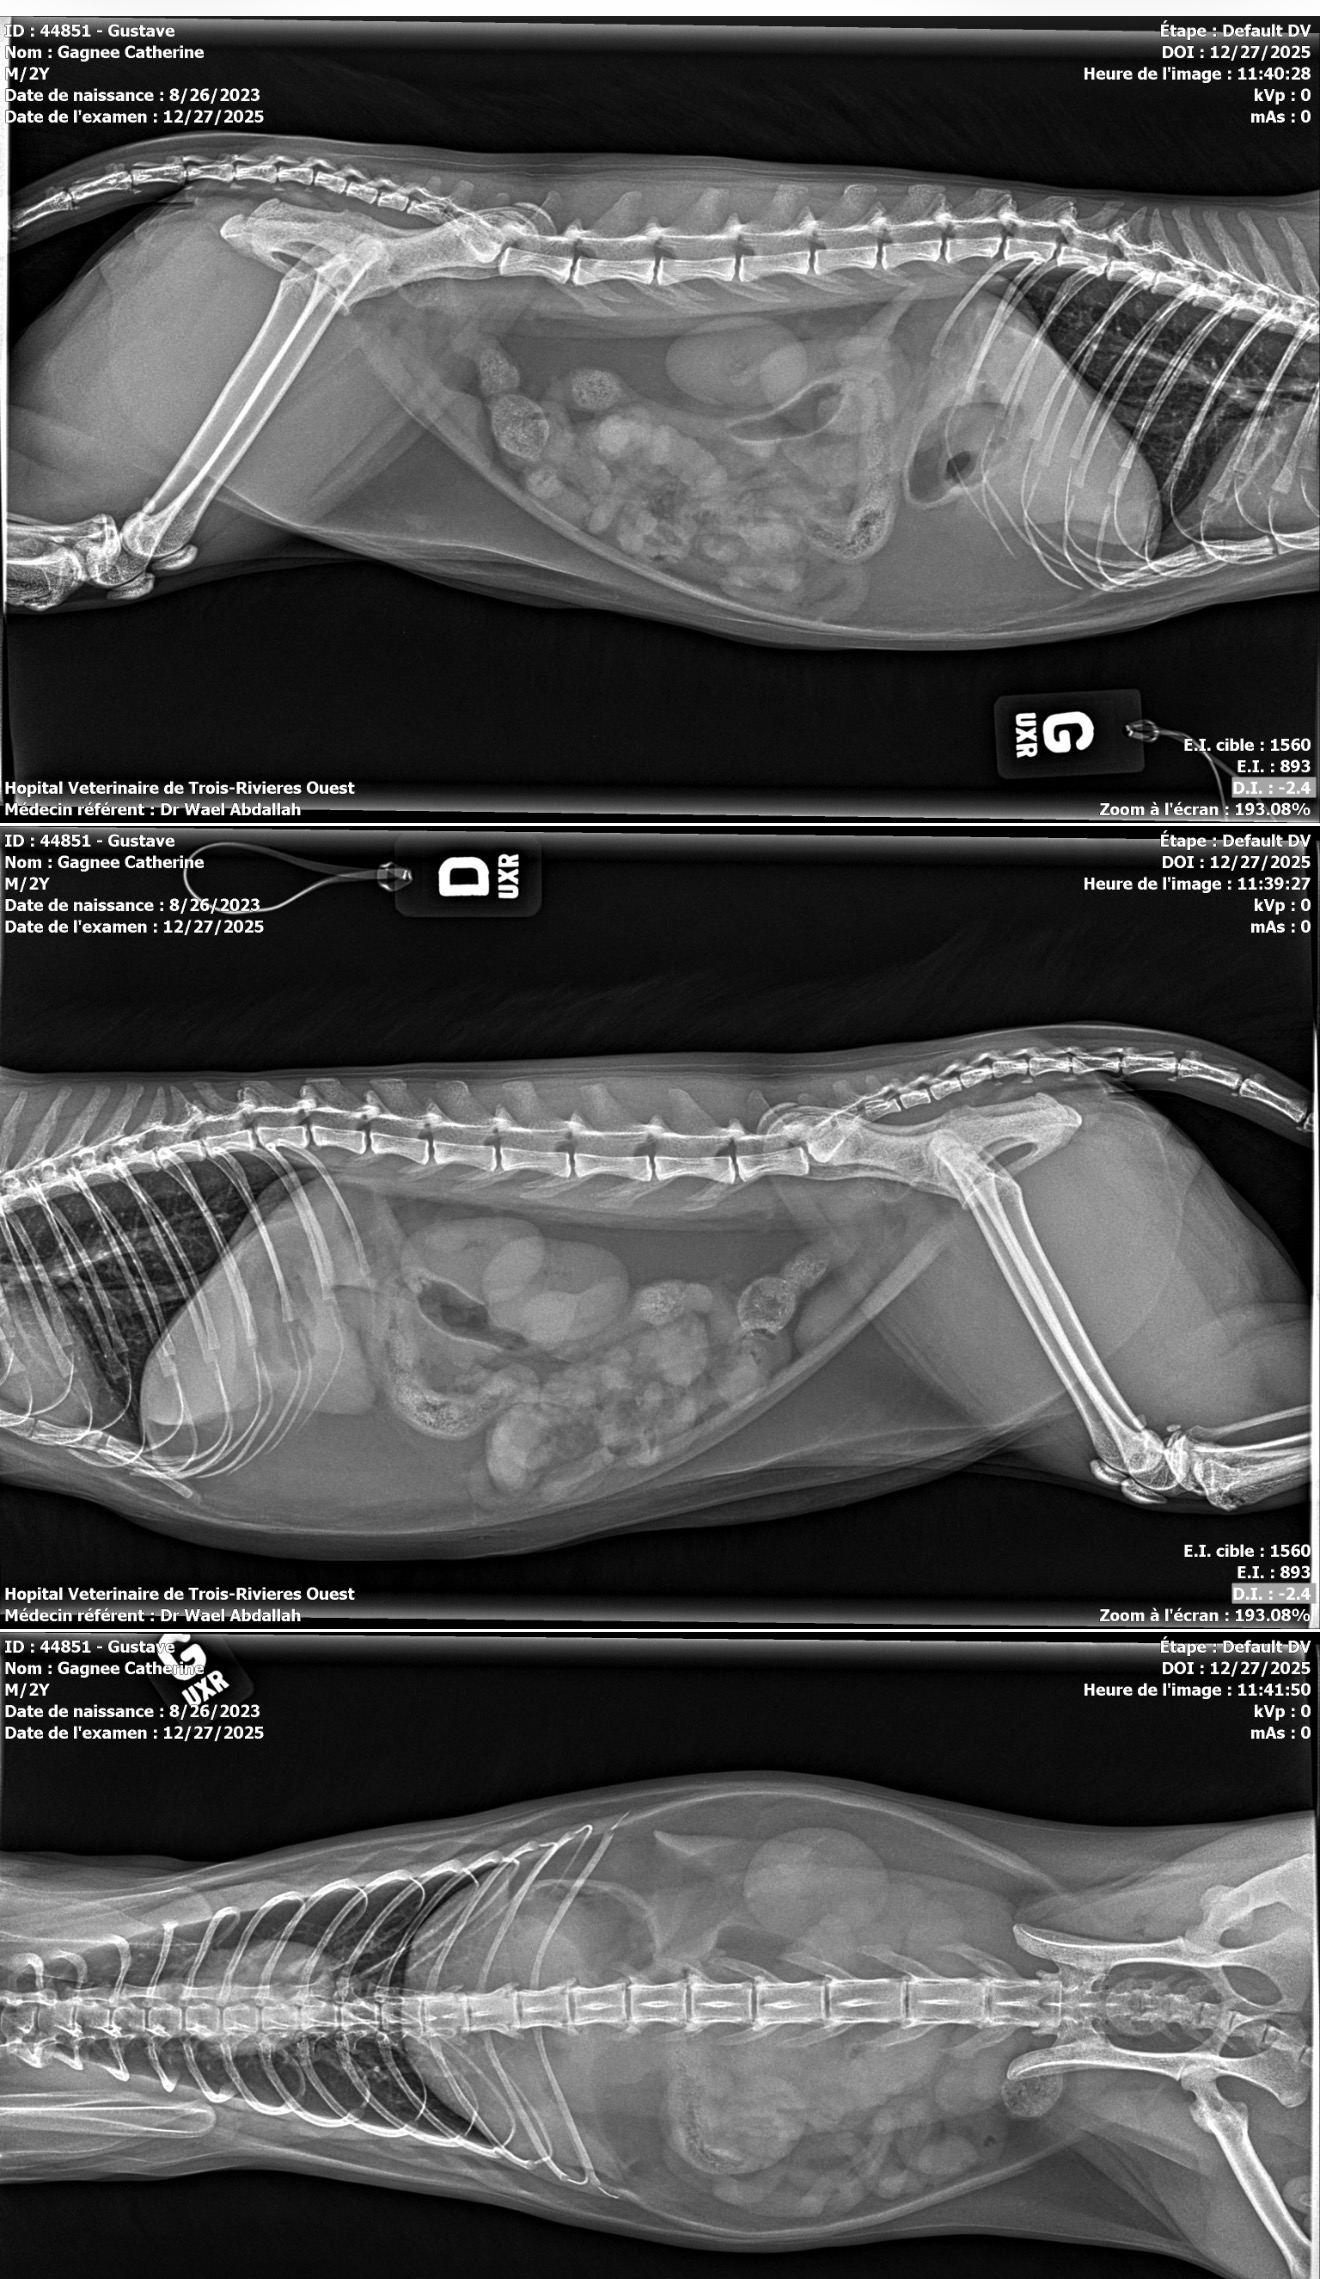

Our cat Gustave, only 2 years old, ingested a foreign object and urgently needs emergency surgery to remove it and save his life.

Notre chat Gustave, âgé de seulement 2 ans, a ingéré un corps étranger et a besoin d’une chirurgie d’urgence pour le retirer et lui sauver la vie.